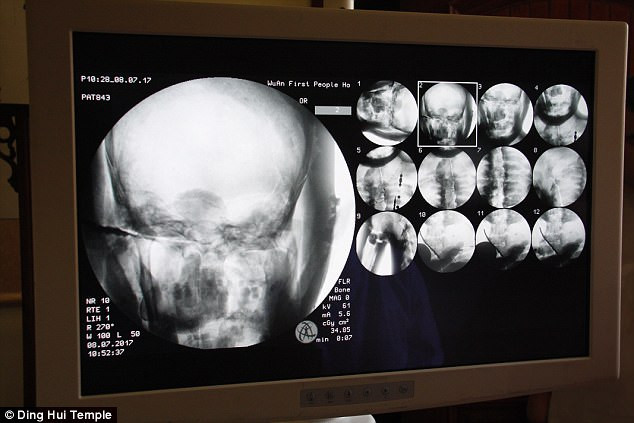

Vào năm 2017, các chuyên gia tiến hành chụp CT cho xác ướp mạ vàng thiền sư Ci Xian nổi tiếng Trung Quốc. Cuộc kiểm tra được tiến hàng ngay tại chùa Dinghui, ở Vũ Hán, phía bắc tỉnh Hà Bắc.

Kết quả chụp CT cho thấy thi hài của thiền sư Ci Xian còn nguyên vẹn đến mức khó tin.

Đặc biệt, hàm trên, răng trên, xương sườn và các khớp của thiền sư Ci Xian vẫn hoàn chỉnh giống như của người mới qua đời.

Điều này cho thấy xác ướp thiền sư Ci Xian ở trong tình trạng rất tốt, không có dấu hiệu bị phân hủy.